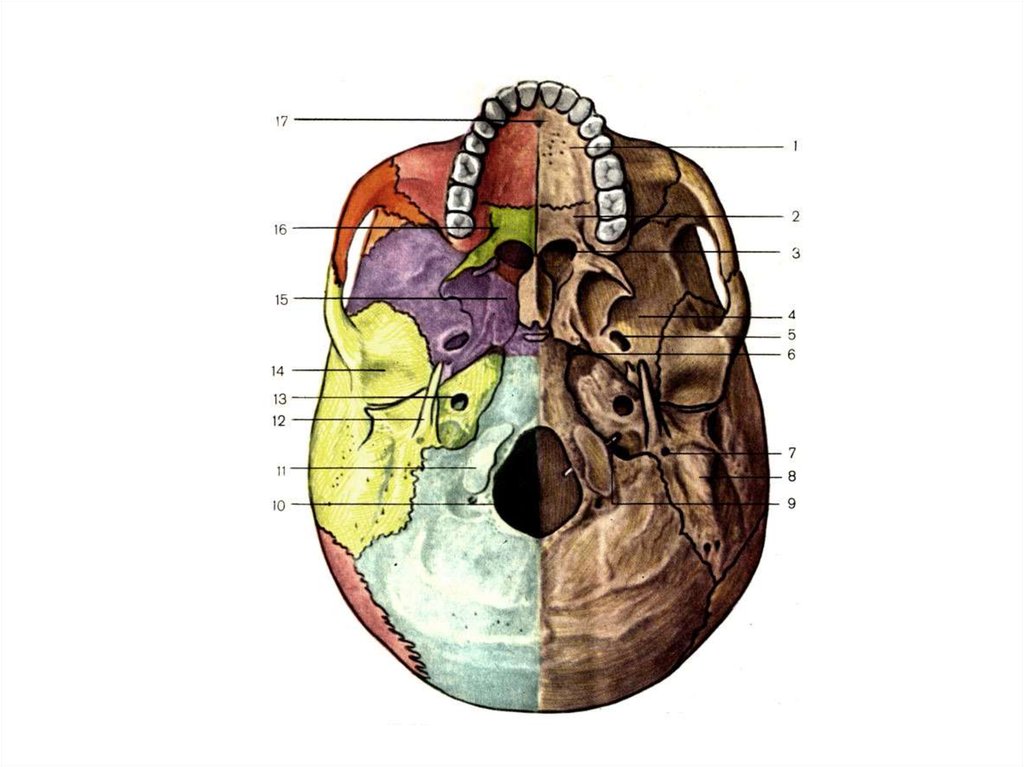

Анатомические детали: Фотографии топографии черепа с нижнего вида

Раздел: Альбом идей